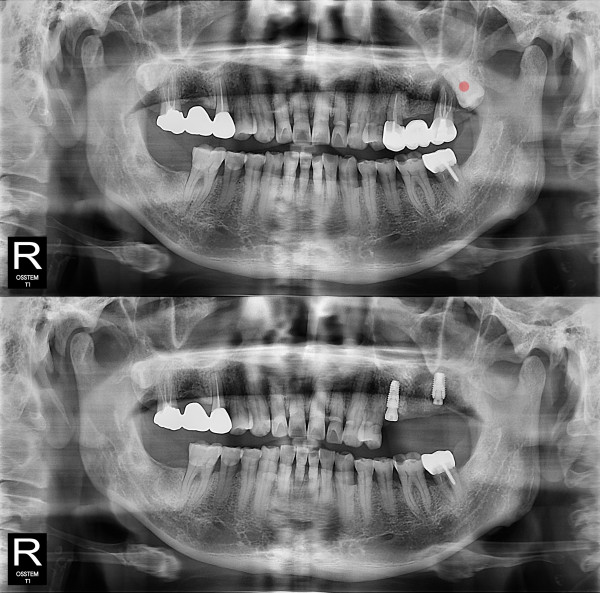

사랑니발치 완전 매복 사랑니

826e40416d712e6cd444a78bde93df4b_1767857243_6817.jpg